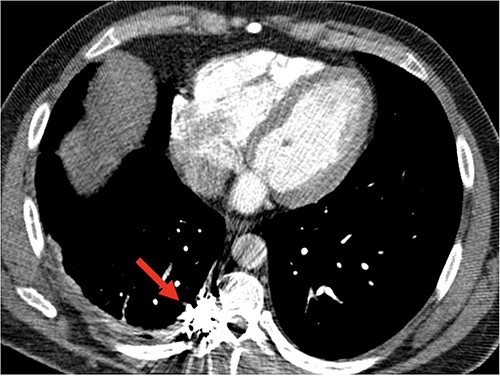

Postoperatively, the chest tube was removed on Day 2, and the patient was discharged to home. The following week, a chest X-ray showed no accumulation of hemothorax. Five weeks following surgery, a repeat CT angiogram demonstrated a stable right T9 intercostal artery embolization coil pack without further evidence of aneurysm or AVM (Fig. 4). The patient was referred to the genetics counseling team for an ongoing follow-up.

Follow-up CT angiogram demonstrated a persistent occlusion of aneurysm, noted by arrow, and resolution of the hemothorax.